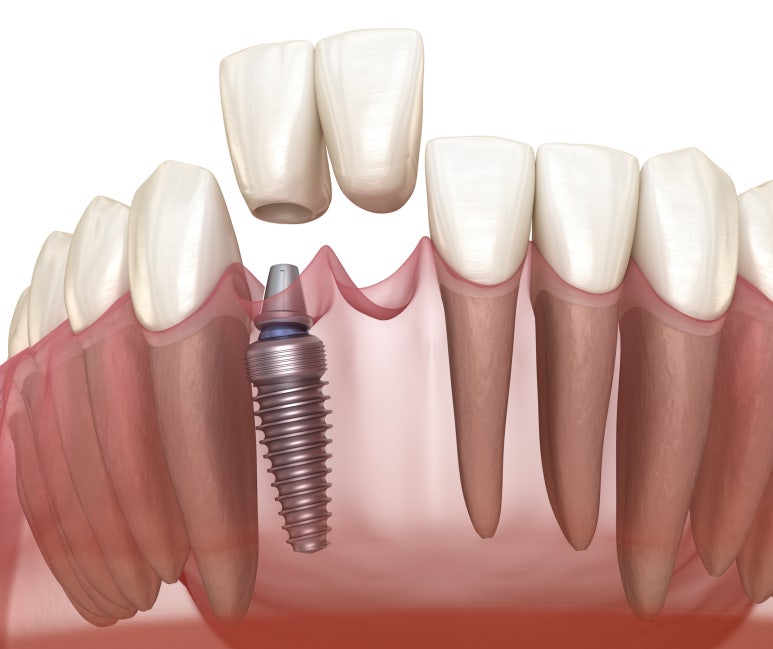

간단히 설명드리면 얼굴뼈 안쪽의 빈 공간을 만들고 있는 얇은 막을 들어올려 뼈이식을 통해

임플란트 픽스처가 식립될 기반을 만들어준 후 임플란트를 식립하는 수술을 상악동거상술을 동반한 임플란트라고 합니다.

만약 이를 고려하지 않고 픽스처를 식립하면 픽스처에 의해 해당 막에 구멍이 뚫리면서

숨을 쉴 때 공기가 새거나 코피가 나거나 염증이 생기는 등 부작용이 있기 때문에 진행되는 수술입니다.

계란 껍질 속 얇은 막을 들어올리는 만큼 굉장히 섬세하고 정교한 기술을 필요로 하기 때문에 난이도도 높고 어려운 수술 중 하나입니다.